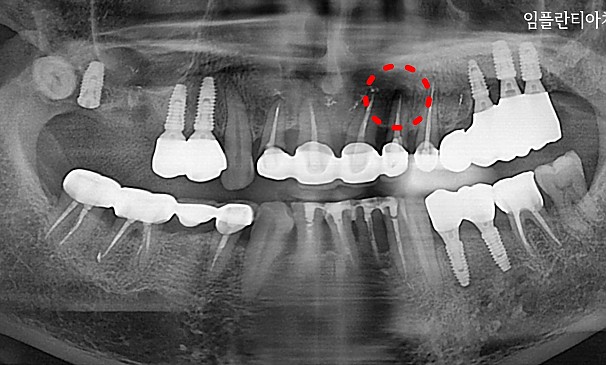

뿌리염증 제거술란?

치아 뿌리 끝에 염증이 생긴 경우는 몇 가지의 원인이 있습니다. 교합문제나 다른 자연 발생적으로 생긴 염증일 수 있고,

이미 신경 치료된 치아가 어떤 이유에서 다시 감염 되었을 때도 뿌리에 염증이 생길 수 있습니다. 염증이 생긴 원인과 염증 범위에 따라 여러 가지 형태로 치료할 수 있습니다.

강OO님 전후사진 | 치료 기간 : 1주

치료 전